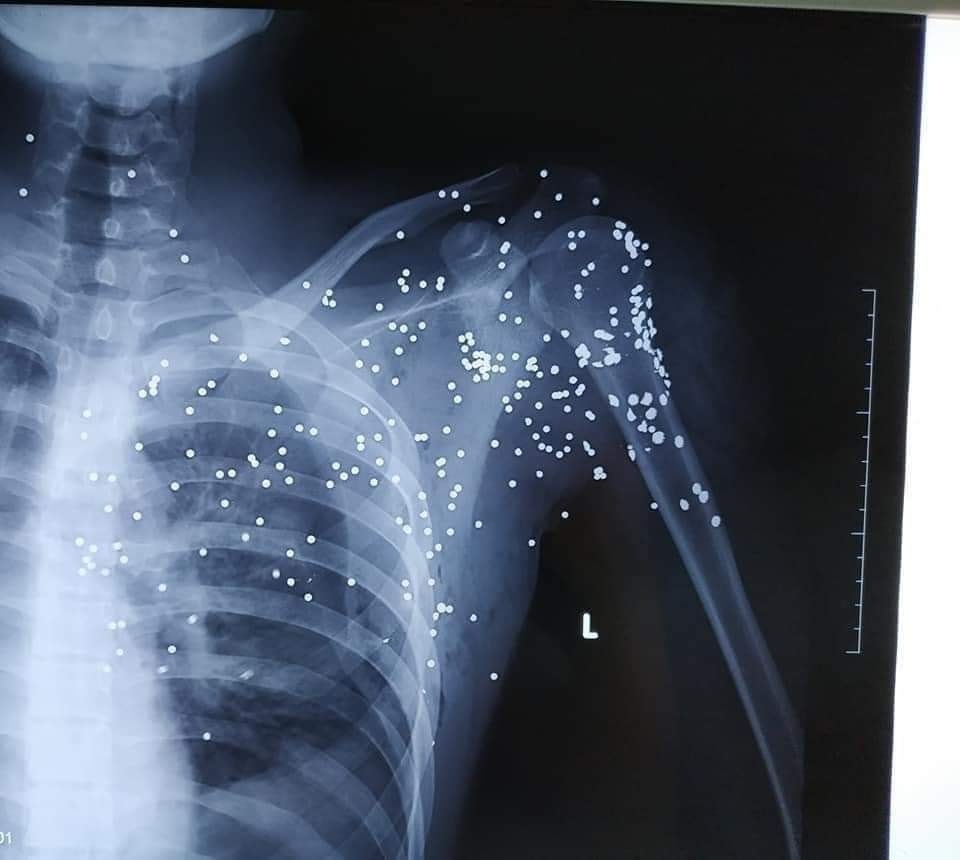

Bác sĩ đếm được trên người Hoàng có khoảng 60-70 vết đạn và cho biết sẽ không thể gắp hết số đạn này ra khỏi cơ thể nạn nhân. Ảnh: Gia đình cung cấp.

Bác sĩ đếm được trên người Hoàng có khoảng 60-70 vết đạn, chưa tính tới những viên đạn chồng lên nhau, bị che khuất mà hình ảnh chụp X-quang không thể thấy được.